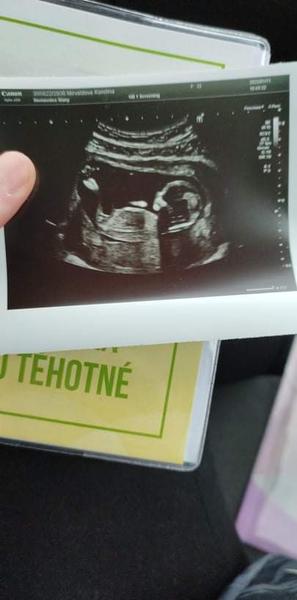

@kaseenka mám ten samý problém, také by mě zajímalo, nedočkavá 😂 prý kluk, ale já to nepoznám. Tipnul by si někdo?

@karolina226 mě to spíš přijde na holčičku